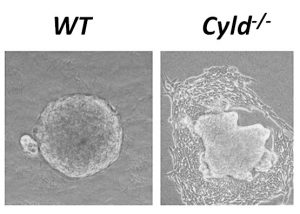

Τίτλος Ερευνητικού Έργου: Διερεύνηση του ρόλου του ογκοκατασταλτικού γονιδίου CYLD στην επιθηλιακή προς μεσεγχυματική μετατροπή

Επιστημονικός Υπεύθυνος: Μόσιαλος Γεώργιος